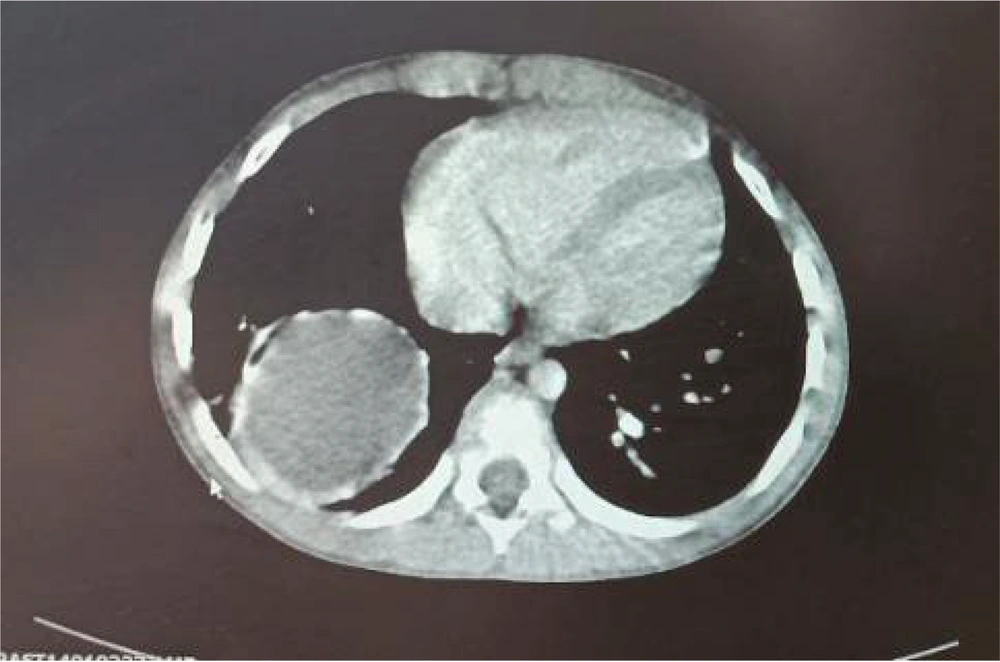

Chest and abdominal X-rays were performed to evaluate the abdominal pain and cough. The CXR revealed a suspicious lung finding (Figure 2). A computed tomography (CT) scan was requested to assess the lung lesion, and a hydatid cyst was incidentally diagnosed in the right lower lobe (Figure 3). The patient was treated with antibiotics for the UTI, and pre-surgical evaluations for the hydatid cyst were conducted. A cardiac consultation revealed mild pulmonary hypertension (systolic pulmonary arterial pressure: 40 - 45 mmHg), right ventricular dilation, right atrial dilation, and moderate tricuspid regurgitation on echocardiography. The CT angiography confirmed the diagnosis of PAPVC.

Hydatid cysts are caused by Echinococcus granulosus and are common in individuals involved in farming or husbandry, with transmission via the fecal-oral route. Pulmonary involvement is more common in children than adults, particularly in the lower lobes and especially the right lobe. Patients may be asymptomatic, with common clinical manifestations including chest pain, hemoptysis, and cough (14, 15). Our patient had a hydatid cyst in the right lower lobe of the right lung and was asymptomatic, with only occasional coughs reported by his mother.

Data on the incidence rates of hydatidosis are regional. A study by Saghafipour et al. reported an incidence rate of 6.81 per 100,000 people over 8 years (16). Mustapayeva et al. found the incidence rate of hydatidosis in Kazakhstan from 2007 to 2016 to be ≤ 0.1% (17). Simple chest radiography (CXR) is the first diagnostic modality for pulmonary hydatidosis. If findings are inconclusive, a pulmonary CT scan can aid in detection (18). We observed a halo in the CXR of our case, prompting a CT scan that confirmed pulmonary hydatidosis. Surgery is the main treatment for pulmonary hydatidosis, with the surgical technique depending on factors such as cyst location, surgeon’s decision, and cyst wall tissue (19, 20). Our case underwent surgery for lung hydatidosis.